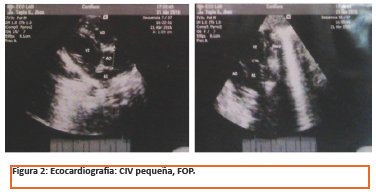

El enfisema lobar congénito (ELC), es una malformación pulmonar rara. Se trata de una sobre distención de uno o más lóbulos pulmonares. Las causas principales son la deficiencia del desarrollo del cartílago bronquial y la obstrucción bronquial de tipo valvular generalmente causada por estenosis bronquial idiopática. El tratamiento, en general es quirúrgico. Laboratorios de ingreso normales. Ecocardiografía: Dextro posición cardiaca en situs solitus por desplazamiento de una masa, CIV, FOP. Ecografía Diafragmática y abdominal normal. Colon por enema: Marco colonico buen pasaje localizado en topografía habitual. TAC Tórax múltiples quistes en campo pulmonar izquierdo. Se realiza lobectomía inferior izquierda. Histopatología confirma enfisema lobar congénito. Es dado de alta a los 10 días posquirúrgico.

desvía el mediastino además la ecocardiografía muestra que el cuadro se acompaña de cardiopatía (CIV, FOP) lo que es característico de esta patología.